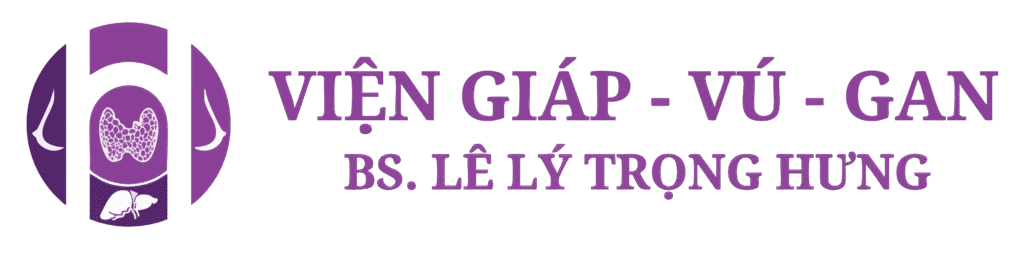

Kết quả chụp nhũ ảnh

- Vú phải:

¼ trên ngoài, lan toả trong mô vú có nhiều nốt vi vôi đa đậm độ, đa hình dạng: tròn, vô định hình, và pleomorphic; kèm có vùng xáo trộn cấu trúc ¼ trên ngoài vị trí 8-9 giờ cách núm vú 5cm, kích thước #18x25mm. - Vú trái:

Không ghi nhận khối u bất thường, xáo trộn cấu trúc, dày da hay co kéo núm vú. Rải rác mô vú có vài nốt vi vôi hoá dạng chấm đậm độ thấp.

Chẩn đoán nhũ ảnh

Tổn thương vi vôi hoá lan toả 1 vùng trên nhũ ảnh với hình thái nghi ngờ được xếp loại BIRADS 4C.